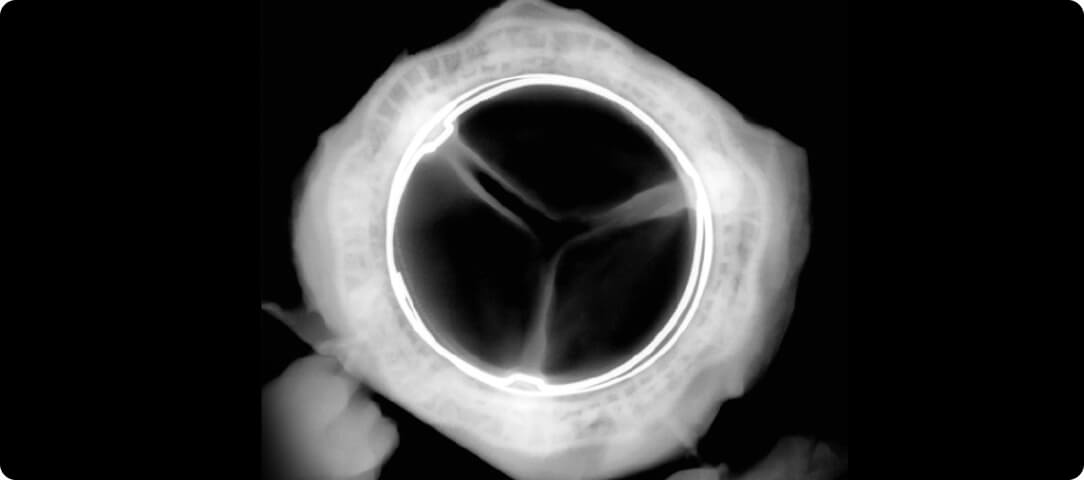

The unique design of the MITRIS RESILIA valve mimics the shape of the heart's natural mitral valve opening, allowing it to handle the high pressure of blood flowing through the mitral valve.

Explanted valves from an animal study1 showing less calcium build-up in the valve with RESILIA tissue compared to the valve with regular tissue.*